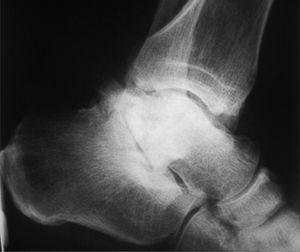

Hemos realizado tan sólo 1 caso debido a una pseudoartrosis (figs. 11 y 12), que se complicó posteriormente con una osteomielitis aguda por lo que se le realizó los 3 tiempos de Papineau. En líneas generales, la talectomía no ha demostrado buenos resultados.

Fig. 12. --Pseudoartrosis y NAV en fractura de cuello de astrágalo. Artrodesis tipo Blair

Fig. 12. --Pseudoarthrosis and avascular necrosis in a fracture of the astragalus neck. Blair-type arthrodesis.